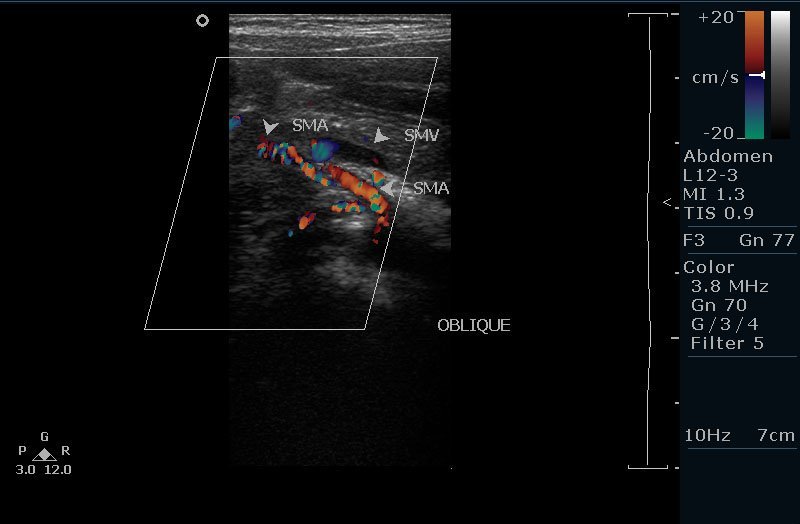

A 3-year-old boy with recurrent abdominal pain and vomiting was diagnosed with midgut volvulus, a complication of malrotation, using ultrasound. The “whirlpool sign,” indicative of twisted intestines, was observed. This case highlights the importance of ultrasound in diagnosing this condition, especially in children with atypical presentations. Learn more about the clinical presentation, ultrasound findings, and surgical management of midgut volvulus.